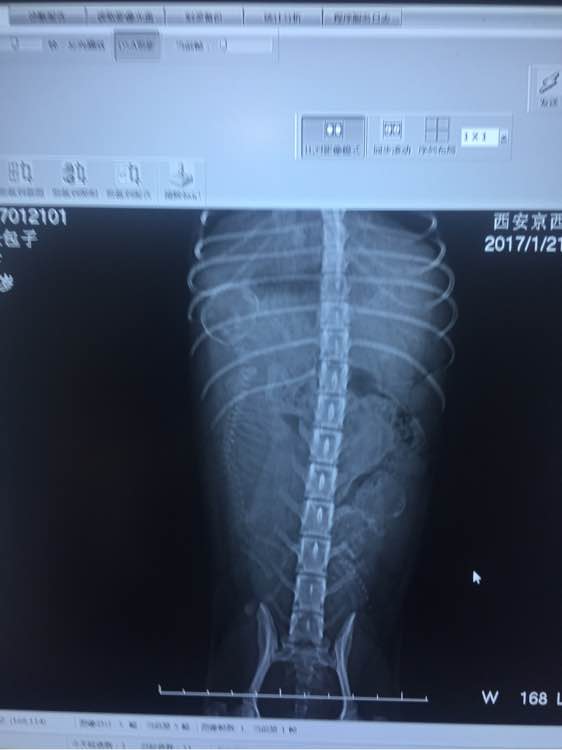

医生拍了片之后,告诉我说,小包子的说不敢再补了,小狗狗一个发育过好,一个发育不良,会影响发育不良狗宝宝的生命安全,医生嘱咐往后的日子不能给狗狗没事加鸡胸肉或者鸡蛋了!要老老实实的吃狗粮了~

刚刚医生把小狗狗的头围发给我了!我感觉是个大头宝宝,会不会难产,每天都很焦虑~